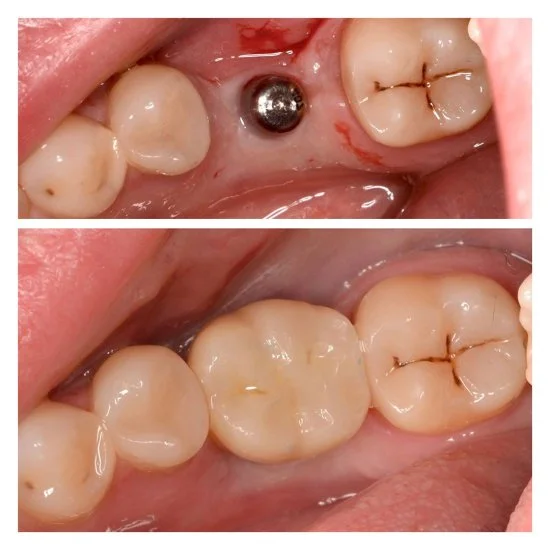

Efekty leczenia